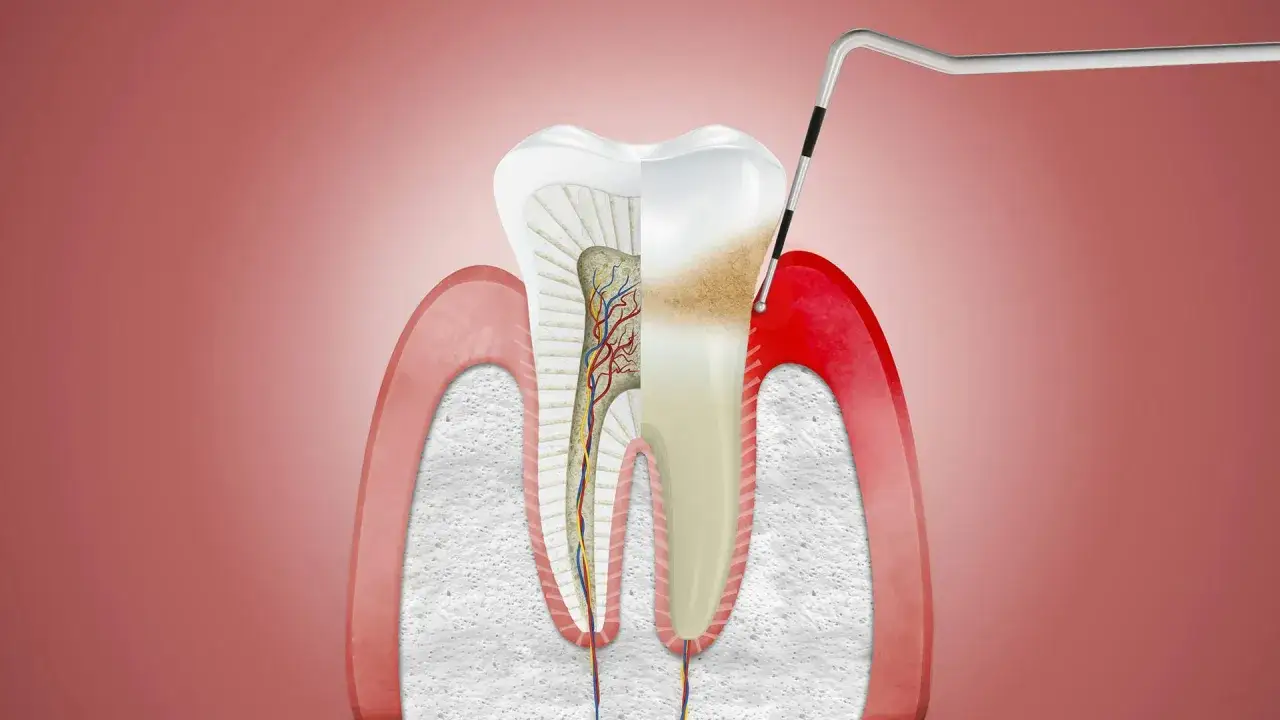

Niestety, nieleczona próchnica jest najczęstszą przyczyną ropni u dzieci. Kiedy ubytek próchnicowy staje się głęboki, bakterie przenikają do miazgi zęba – czyli jego "serca", gdzie znajdują się nerwy i naczynia krwionośne. Dochodzi wtedy do zapalenia miazgi, a następnie do jej martwicy. Bakterie z martwej miazgi mogą przedostać się poza wierzchołek korzenia zęba, do kości i tkanek otaczających, tworząc ropień. Dotyczy to zarówno zębów mlecznych, jak i stałych.

Drenaż ropnia i usunięcie źródła zakażenia

Podstawą leczenia jest zawsze drenaż ropy. Dentysta wykonuje niewielkie nacięcie w miejscu ropnia, aby umożliwić swobodny odpływ nagromadzonej wydzieliny. To natychmiastowo przynosi ulgę w bólu i zmniejsza obrzęk. Równocześnie, a często nawet ważniejsze, jest usunięcie pierwotnej przyczyny zakażenia. Może to być opracowanie i wypełnienie próchnicowego zęba, usunięcie martwej miazgi lub inne procedury mające na celu eliminację bakterii.

Leczenie kanałowe zęba mlecznego lub stałego, gdy można go uratować

Jeśli ząb, który jest przyczyną ropnia, nadaje się do uratowania, dentysta może podjąć decyzję o leczeniu kanałowym. Polega ono na usunięciu zainfekowanej lub martwej miazgi z wnętrza zęba, dokładnym oczyszczeniu i zdezynfekowaniu kanałów korzeniowych, a następnie ich szczelnym wypełnieniu. Procedura ta może być przeprowadzona zarówno w zębach mlecznych, jak i stałych, aby zachować ząb w jamie ustnej.